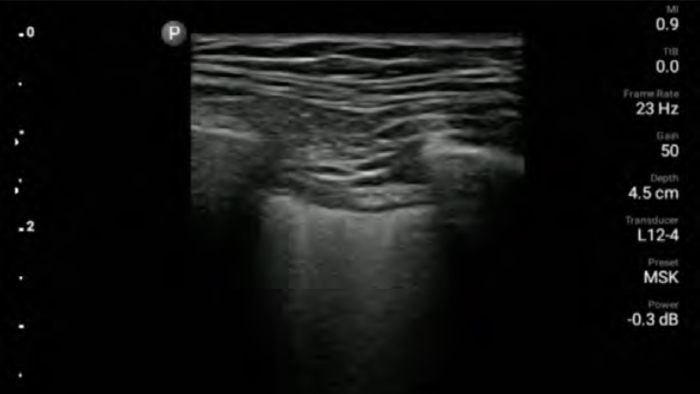

• 12 to 4 MHz extended operating frequency range

• Aperture size: 34mm

• 2D, steerable color Doppler, M-mode, advancedXRES and multivariate harmonic imaging, SonoCT

• High resolution imaging for shallow applications: soft tissue, vascular, superficial, musculoskeletal and lung

• Center line marker

• USB-C transducer with replaceable cable